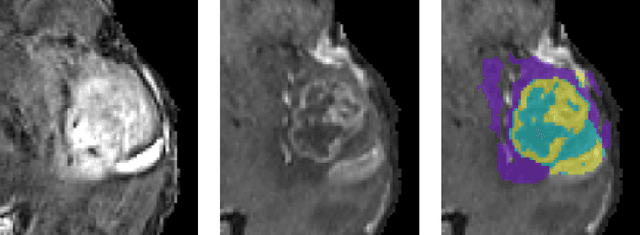

Abstract:Quantitative analysis of brain tumors is critical for clinical decision making. While manual segmentation is tedious, time consuming and subjective, this task is at the same time very challenging to solve for automatic segmentation methods. In this paper we present our most recent effort on developing a robust segmentation algorithm in the form of a convolutional neural network. Our network architecture was inspired by the popular U-Net and has been carefully modified to maximize brain tumor segmentation performance. We use a dice loss function to cope with class imbalances and use extensive data augmentation to successfully prevent overfitting. Our method beats the current state of the art on BraTS 2015, is one of the leading methods on the BraTS 2017 validation set (dice scores of 0.896, 0.797 and 0.732 for whole tumor, tumor core and enhancing tumor, respectively) and achieves very good Dice scores on the test set (0.858 for whole, 0.775 for core and 0.647 for enhancing tumor). We furthermore take part in the survival prediction subchallenge by training an ensemble of a random forest regressor and multilayer perceptrons on shape features describing the tumor subregions. Our approach achieves 52.6% accuracy, a Spearman correlation coefficient of 0.496 and a mean square error of 209607 on the test set.